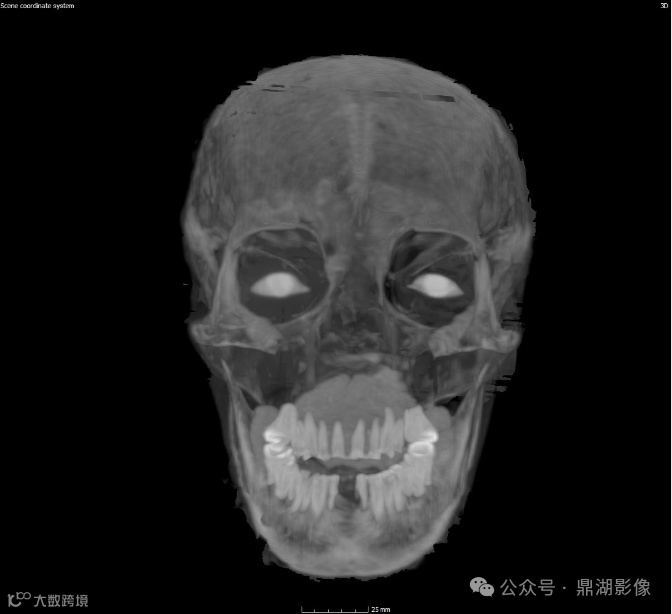

颅脑图像

现在可以断定她去世时的年龄为30多岁或40岁出头;

她失去了几颗牙齿,剩余牙齿严重磨损,这表明她吃的食物中含有对牙釉质有损害的散沙颗粒;

扫描结果还显示,Chenet-aa夫人的眼窝中还植入了辅助眼球。